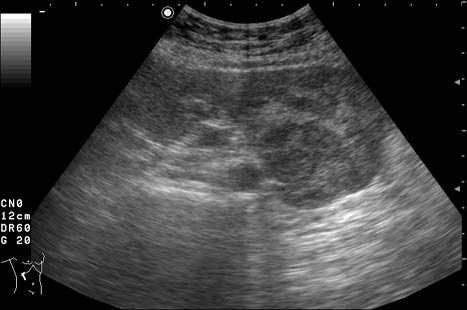

Женщина 72 лет. При УЗИ выявлены два аваскулярные образования: в нижнем полюсе правой почки и у верхнего полюса почки.

Уникальность случая в том, что эти изменения - БЕЗ ДИНАМИКИ с 2005 года.

Опухоль почки?

Опухоль почки и надпочечника.

У пожилых людей опухли чаще всего растут медленно.

Случай из практики - бабушка 73 лет "наблюдала" опухоль почки более 5 лет. После того как было выполнено УЗИ, гордо предъявила старую картинку, где опухоль была миллиметр в миллиметр со свежей картинкой. Я решил, что это доброкачественное образование, например онкоцитома.

Бабушку прооперировали, заключение - почечно-клеточный рак (RCC).

Без допплера явно опухоль почки